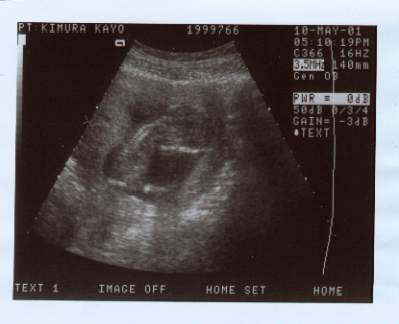

Kayo's Baby First Photo

Here is the first photo of Kayo's Baby.

I must admit that she looks just like her father.

Her present due date is November 6, 2001. We are presently planning to name her Sandra Coyote Sloan.